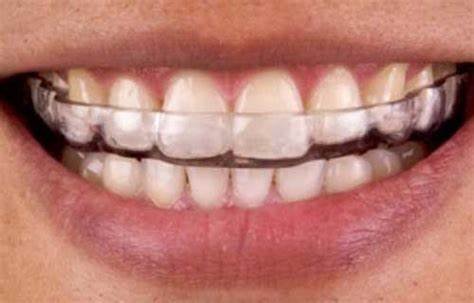

Occlusal Splints

- BioSplint™ (BioResearch Associates)

- Custom-designed splints with computerized occlusal analysis

- Digital design allows precise adjustments

- Integration with T-Scan™ technology for occlusal force analysis

- Price range: $400-600 for dentist, $800-1,200 for patient

- Comfort H/S™ Occlusal Splint (Glidewell Laboratories)

- Hard acrylic outer layer with soft inner lining

- Balanced occlusion design for even force distribution

- Available with various thickness options

- Price range: $175-250 for dentist, $450-650 for patient

- NTI-tss™ (National Dentex Laboratories)

- Anterior-only splint design

- Targets reduction of parafunctional muscle activity

- Simple and minimally invasive

- Price range: $75-125 for dentist, $200-350 for patient